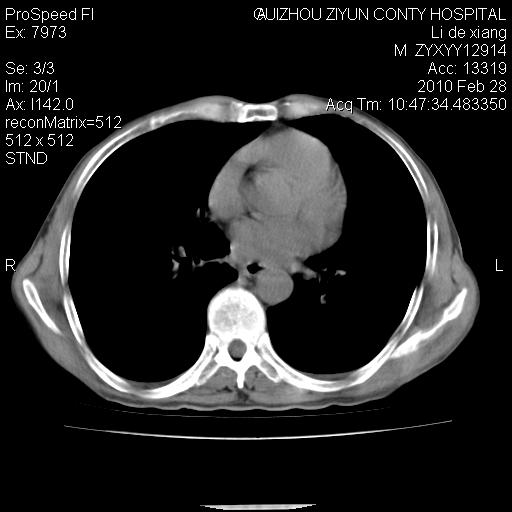

标题: CT24776:男 71Y 咳嗽咳痰胸痛两月,伴声音嘶哑。 [打印本页]

标题: CT24776:男 71Y 咳嗽咳痰胸痛两月,伴声音嘶哑。

左侧中央型肺癌伴左肺上叶阻塞性肺炎及节段性不张可能性大,建议纤支镜检查!

左侧中央型肺癌伴左肺上叶阻塞性肺炎及节段性不张可能性大,建议纤支镜检查!纵隔淋巴结转移.

左肺门部肿块,伴左上肺斑块影,周边模糊,支持左肺中央型肺癌伴节段性不张及阻塞性肺炎,结合支气管镜检查。

左上叶支气管狭窄,阻塞性病变,肺门肿块,纵隔及肺门淋巴结增大,中央性肺癌